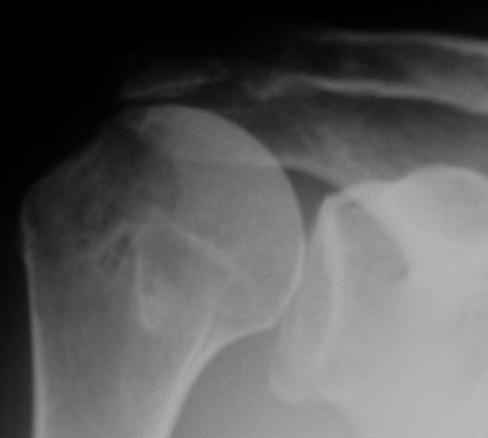

Физический активный мужчина 50 лет в мае 2009 года был оперирован на правом плечевом суставе. Выполнялся открытый шов надостной мышцы и субакромиальная декомпрессия по поводу ее частичного разрыва и импиджмент синдрома III степени. Послеоперационный период протекал без осложнений. Гипсовая иммобилизация в положении отведения плеча до 45 градусов в течение 6 недель.В последующем, несмотря на активные занатия ЛФК, сформировалась приводяще-внутриротационная контрактура оперированного сустава (отведение до 80 градусов, наружная ротация до 15 градусов. Болевого синдрома нет, при пассивном отведении плеча создается впечатление "механического" препятствия движению.На контрольных рентгенограммах складывается впечатление о сформировавшемсся верхнем подвивихе головки правой плечевой кости, как о причине контрактуры. Хотелось бы услышать мнение коллег о такттике дальнейшего лечения.

Верхний подвывих в такой ситуации может быть проявлением ротаторной артропатии, как следствия более массивного, чем частичный разрыв сухожилия надостной мыщцы, повреждения вращательной манжеты. И значит нужно думать о том, насколько полно восстановлена манжета, адекватно ли был расценен объем ее повреждения. Что за шов применялся? Якорных винтов не видно. И почему гипсовая иммобилизация? Есть прекрасные надувные отводящие подушки, позволяющие ранние движения.

В качестве примера - снимки до и после восстановления целостности вращательной манжеты после 3-хмесячной давности полного разрыва. Видно, что верхний подвывих устранен.

К сожалению, более подробной информации из выписного эпикриза почерпнуть не удалось (больной был оперирован, наблюдался и проходил реабилитацию в другом лечебном учреждении. Полностью согласен, что высокое стояние головки плеча, вероятнее всего, свидетельствует о неадекватном восстановлении ротаторной манжеты, к счастью пока без выраженных рентгенпризнаков ротаторной артропатии.